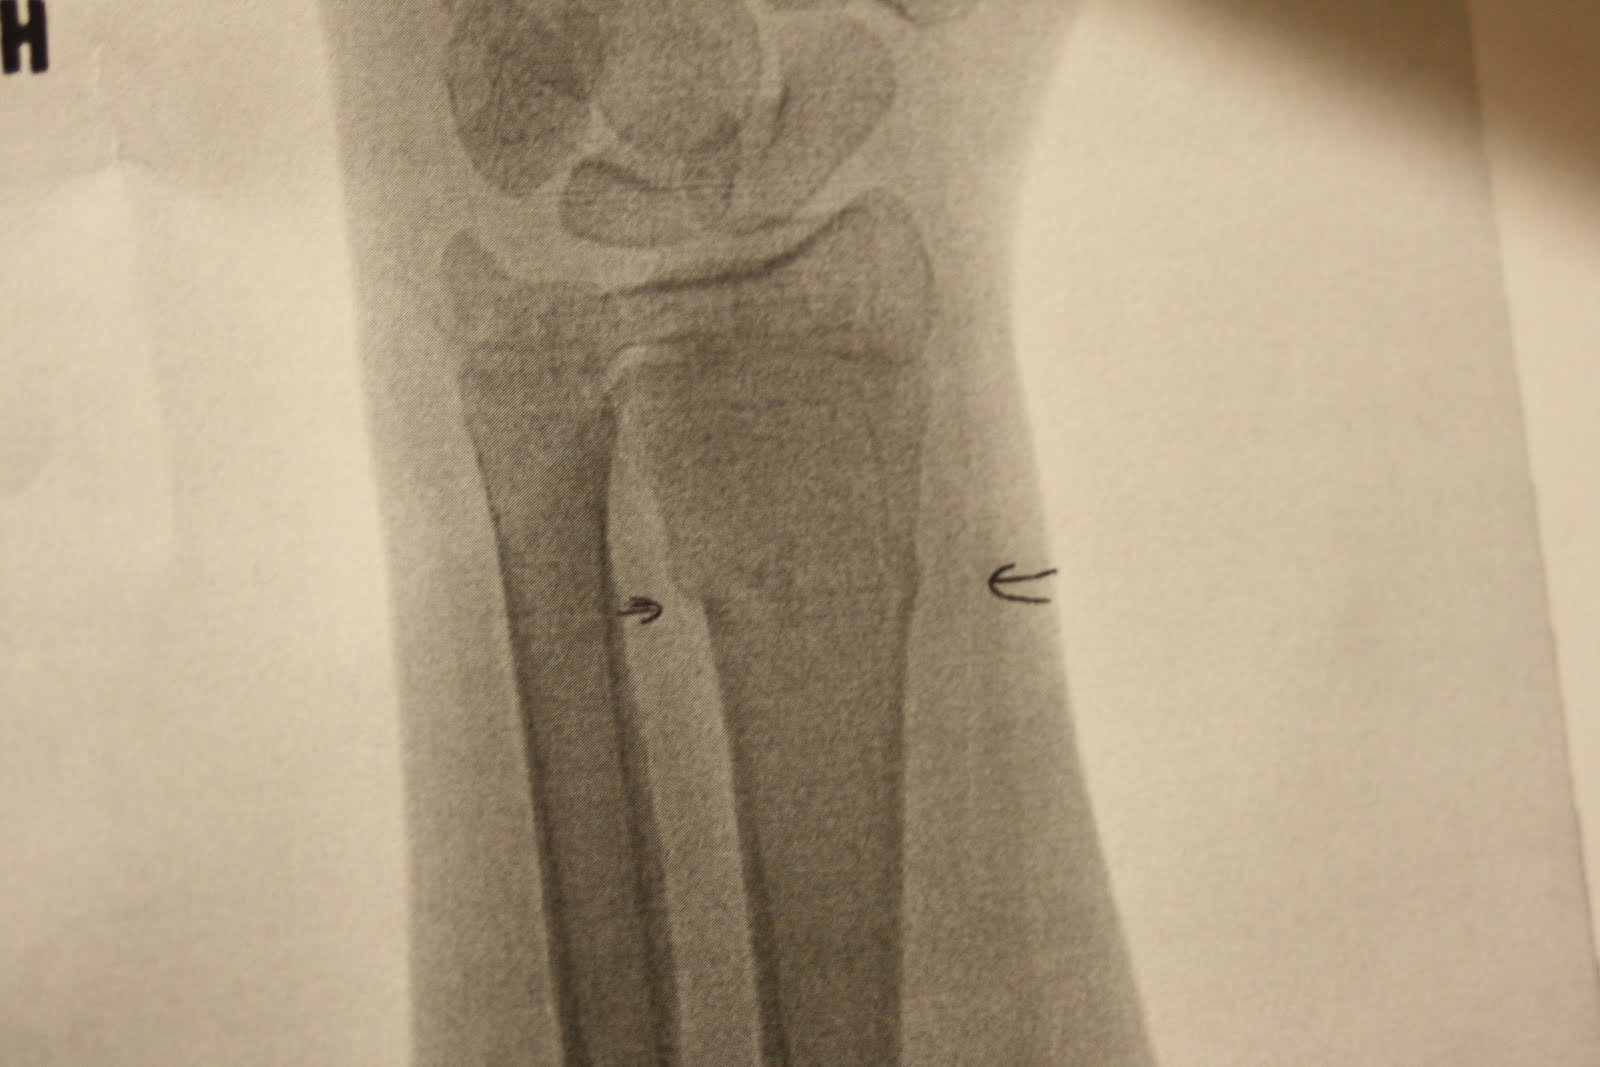

He's got this happening (see the small arrow - those two bones should be one):

And he's got this going on (there's a small line at the arrows - another fracture):

Poor kiddo. I''m just hoping the pills are strong enough to allow him some sleep tonight. We'll be seeing the Ortho tomorrow to set the wrist. The worst thing of all is the fact that we're looking at the right shoulder and left wrist.